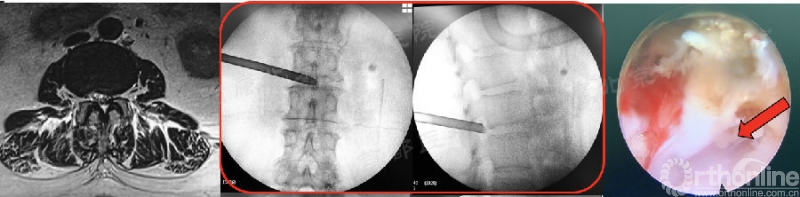

a. 第23例,术前没看CT!

第23例,女,39岁,L5/S1 LDH。腰痛伴右下肢大腿后侧、小腿后侧麻木,直腿抬高试验40°(+)。上台后穿刺针扎不进间盘,依靠一级通道敲进椎间隙。置入通道后几乎看不见椎间盘,全是骨化。

打开PACS看CT,显示椎间盘后缘环形钙化!发现掉入陷阱中。

术中改变思路,用骨刀进行上关节突切除侧隐窝减压,过程很艰苦,减压至黄韧带,下方即是行走神经根。受限于通道大小和镜下工具,没能充分切除钙化间盘。术后患者右下肢麻木酸痛症状部分缓解。此例为早期30例中效果不满意的2位患者之一。